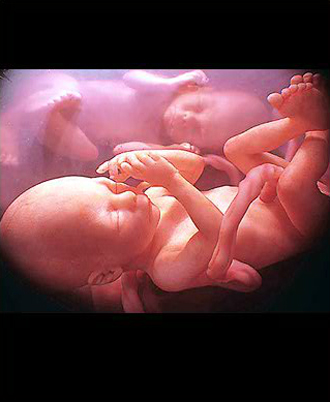

- 초기 정밀 초음파

- 복부 초음파